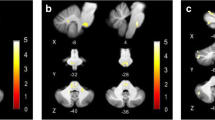

The overlap of all individual lesion–functional connectivity network (FCN) maps was calculated to evaluate the common network structure for cortical lesions that caused vertigo. Figure 4 shows the overlap of eight or more FCNs in the group with vertigo. The individual lesion FCNs are shown in Supplementary Fig. 2. The common subcortical components of the FCNs include the vestibular nuclei (VN), the cerebellar vestibular and ocular motor representations in lobules IX (nodulus, uvula) and X (flocculus/paraflocculus). Cortical network hubs included the PIVC, bordering posterior insular cortex (PIC) and adjacent superior temporal gyrus but also more distant vestibular multisensory areas, such as the ventral intraparietal area (VIP), motion-sensitive areas MT+ in the temporal lobe and cingulate visual sulcus (CSv) and ocular motor areas of the parietal (lateral parietal area—LIP) and frontal lobes (frontal eye fields, FEF, and dorsolateral prefrontal cortex, DLPFC). Additional connectivity was also seen with primary somatosensory and visual cortex. However, when the seed of the lesion without vertigo overlaps was considered individually (lesions 11, 12), a strikingly similar network emerged (Fig. 5).

Overlap of functional connectivity networks (FCN) of the individual lesions (positive correlations with the lesion site). The individual lesion network maps are thresholded at p < 0.001, FWE corrected for multiple comparisons after calculating 10,000 permutations using TFCE. The figure shows an overlap of eight or more cases. Common vestibular network hubs to all lesions include the cerebellar vestibular and ocular motor representations in lobules IX (nodulus, uvula), lobule X (flocculus/paraflocculus), the vestibular nuclei (VN), the thalamus, the parieto-insular vestibular cortex (PIVC; includes insular gyri IV, V (anterior and posterior long insular gyri), area OP2, and retro-insular cortex), the posterior insular cortex (area PIC), motion-sensitive temporal and cingulate areas MT + and CSv (cingulate visual area), ocular motor and vestibular intraparietal areas LIP and VIP (lateral and ventral intraparietal area), the frontal and cingulate eye fields (FEF, CEF). The color bar gives the number of overlapping lesion FCNs

Shows the FCN of the right- and left-sided lesions of the posterior insula that did not lead to vertigo/dizziness (n = 10 cases). The FCN observed in these lesions was remarkably similar, involving the vestibulo-cerebellum and the cortical vestibular and ocular motor networks. All results thresholded at p < 0.001, FWE corrected for multiple comparisons on the cluster level after 10 000 permutations using TFCE. The color bar shows t score intensities. IX, X cerebellar lobules IX, X, MT+ motion-sensitive temporal area, PIVC parieto-opercular (retro-)insular vestibular cortex, PIC posterior insular cortex, FEF frontal eye field, CEF cingulate eye field, LIP/VIP lateral/ventral intraparietal area, CsV cingulate visual sulcus